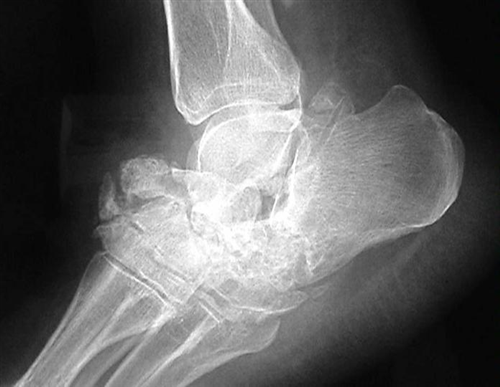

Bệnh khớp Charcot là một tình trạng tiến triển đặc trưng bởi trật khớp, gãy xương bệnh lý và biến dạng nặng ảnh hưởng đến chức năng. Rối loạn này dẫn đến sự phá hủy dần dần xương và mô mềm ở các khớp chịu trọng lượng và ở dạng nghiêm trọng nhất có thể gây ra sự phá vỡ đáng kể cấu trúc xương. Tình trạng này có thể ảnh hưởng đến bất kỳ khớp nào; tuy nhiên, nó xảy ra phổ biến nhất ở chi dưới ở bàn chân và cổ chân.

Bệnh khớp Charcot rất có thể là kết quả của sự kết hợp của các cơ chế này. Bệnh lý thần kinh tự chủ dẫn đến sự tạo xương bất thường, còn bệnh lý thần kinh cảm giác dẫn đến khớp mất cảm giác và dễ bị chấn thương. Khi xương bất thường không có khả năng bảo vệ khớp, xương dần dần bị gãy và khớp bị bán trật.

Loại trừ nhiễm trùng là ưu tiên hàng đầu trong xử lý cấp tính. Đếm số lượng bạch cầu là một dấu hiệu không đặc hiệu cho tình trạng viêm và nó có thể tăng ở những bệnh nhân mắc bệnh khớp Charcot và không bị nhiễm trùng. Tốc độ máu lắng rất hữu ích nhưng không đủ nhạy để xác nhận sự hiện diện của nhiễm trùng. Protein phản ứng C, một dấu chỉ điểm viêm, là một xét nghiệm đáng tin cậy hơn, với kết quả cao rõ rệt cho thấy tình trạng nhiễm trùng đang hoạt động. Thường rất khó phân biệt giữa nhiễm trùng mô mềm sâu và viêm tủy xương. Sinh thiết xương là phương pháp chắc chắn duy nhất để xác định chẩn đoán viêm tủy xương. Tuy nhiên, CT, MRI hoặc chụp X quang thường được sử dụng. Hạn chế chính là khoảng thời gian tương đối dài từ khi khởi phát đến khi xuất hiện những thay đổi viêm tủy xương điển hình trên X quang.